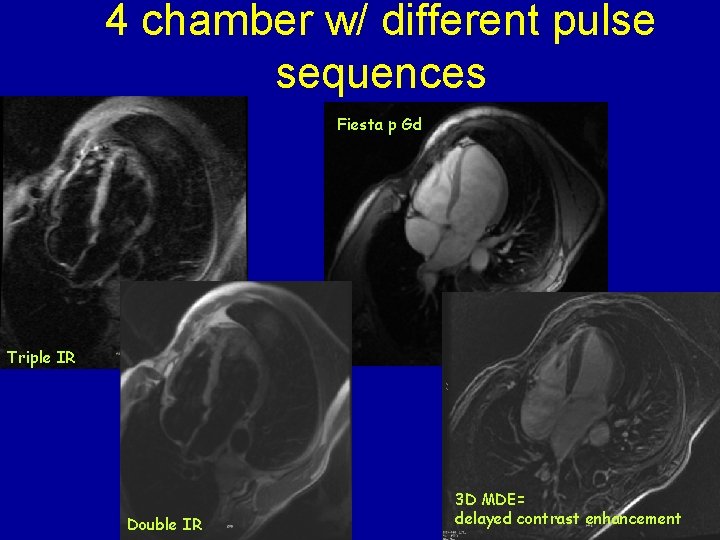

4 chamber w/ different pulse sequences Fiesta p Gd Triple IR Double IR 3 D MDE= delayed contrast enhancement